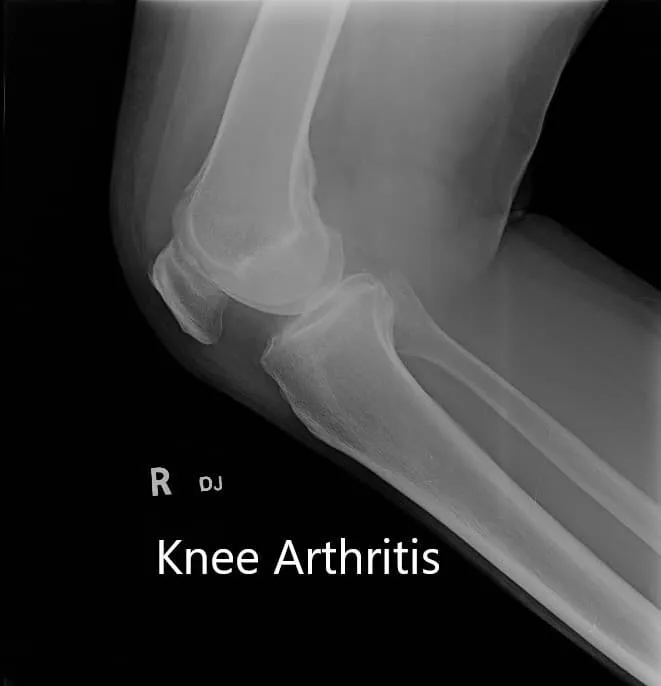

Los estudios de imagen revelaron osteoartritis tricompartmental con cambios degenerativos. Le recomendaron un reemplazo total de rodilla a medida en función de su examen y necesidades. Se debía realizar una tomografía computarizada preoperatoria unas semanas antes de la cirugía.

Radiografía preoperatoria que muestra la visión AP y lateral de la articulación de la rodilla derecha, y vista del horizonte de ambas articulaciones.